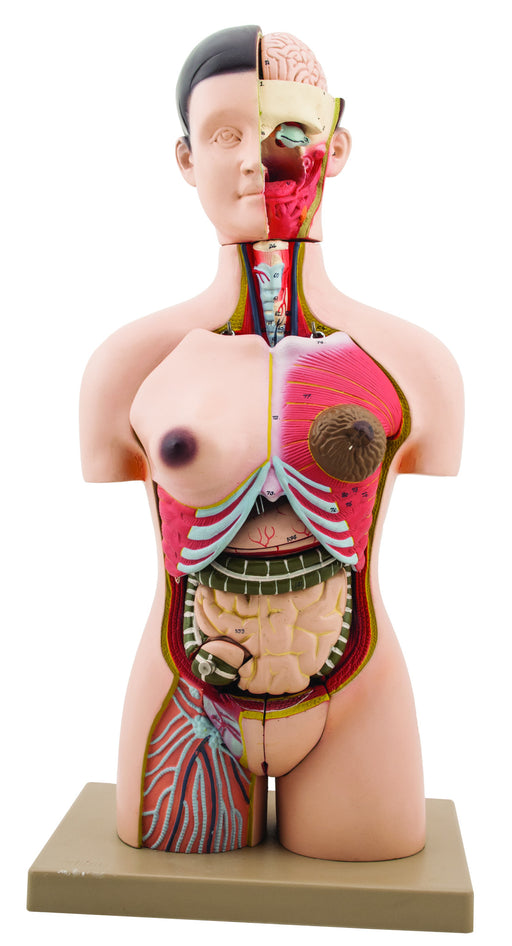

Human Half Muscle Female Torso with Dual Sex Ÿ?? Economy Ÿ?? 17 Parts

The detailed, life size 3D rendering of the human torso with its vibrantly colored anatomy is ideal for studying the structure and function of the ...

View full detailsAM16005 -